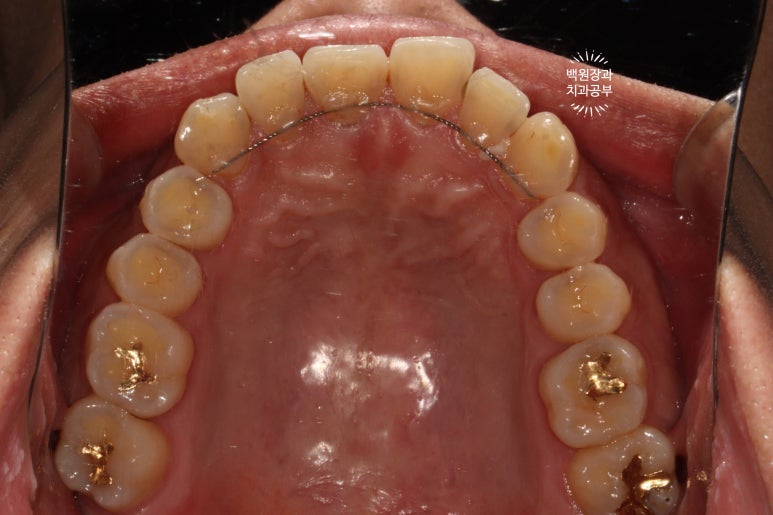

교합면에서 보면, 충치가 뒤에서 봤을 때도 까맣게 보이는구나~ 라고 아실 수 있을겁니다.

잘 보시면, 교정치료 후 유지장치가 있다고 해도 치실을 사용하실 수 있는 것을 보실 수 있습니다.

생각보다 치실을 사용할 수 없다고 생각하는 경우도 대부분 사용 가능한 경우가 많아요~~

레진치료를 받더라도, 잘 유지하기 위해서 인접면 구강위생관리는 필수입니다!!